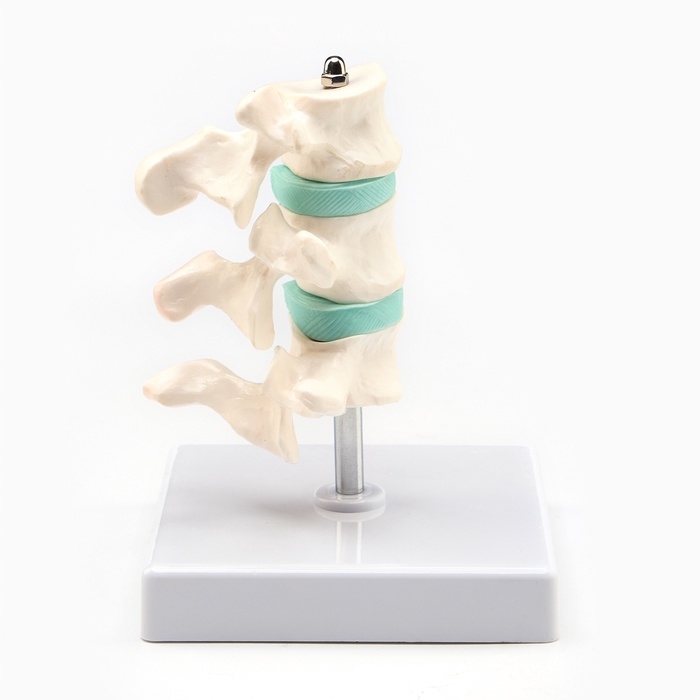

ЕКБ 93

No Brand, артикул: 7072363